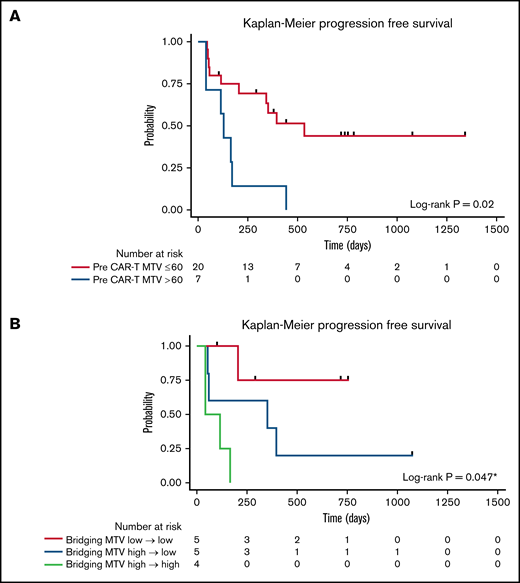

The median time from 18F-FDG PET/CT scan to CD30.CAR-T cell infusion was 12 days (range, 4-35 days). MTV calculated from 18F-FDG PET/CT scans obtained after bridging therapy (if applicable) and before lymphodepletion and CD30.CAR-T cell infusion were evaluated by a twofold, cross-validating analysis. This revealed a trend toward inferior PFS in patients with high pre–CAR-T MTV (P = .07; Table 2). After adjusting for lymphodepletion, high pre–CAR-T MTV was associated with inferior PFS (P = .03). Analyzing pre–CAR-T MTV with a cutoff of 60 mL revealed that high MTV > 60 mL was associated with inferior PFS in both the unadjusted model and after adjustments for lymphodepletion and CAR-T dose (P = .02, 0.01, and 0.006, respectively; Figure 3A). The 1-year PFS estimate was 14% (95% CI: 1%-46%) and 58% (95% CI: 33%-76%) in the high and low baseline MTV groups, respectively.

PFS by baseline MTV. (A) PFS by high (blue) vs low (red) MTV, using a cutoff of 60 mL. (B) PFS by change to MTV with bridging therapy using a cutoff of 60 mL. Low MTV to low MTV (red), high MTV to low MTV (blue), and high MTV to high MTV (light green). *Pairwise P value low to low MTV compared with high to high MTV.

PFS by baseline MTV. (A) PFS by high (blue) vs low (red) MTV, using a cutoff of 60 mL. (B) PFS by change to MTV with bridging therapy using a cutoff of 60 mL. Low MTV to low MTV (red), high MTV to low MTV (blue), and high MTV to high MTV (light green). *Pairwise P value low to low MTV compared with high to high MTV.

The impact of bridging therapy on MTV and subsequent PFS after CD30.CAR-T cell therapy was also evaluated. Patients who had low MTV (≤60 mL) before bridging therapy and continued to have low MTV before CD30.CAR-T cell infusion had the best PFS (1-year PFS 75%; 95% CI: 13%-96%). Patients who had high MTV (>60 mL) that improved with bridging therapy to low MTV before CD30.CAR-T cell infusion had intermediate PFS (1-year PFS 40%; 95% CI: 5%-75%). Finally, patients with high MTV that did not improve to low MTV with bridging therapy had poor PFS (1-year PFS 0%; P = .047; Figure 3B).